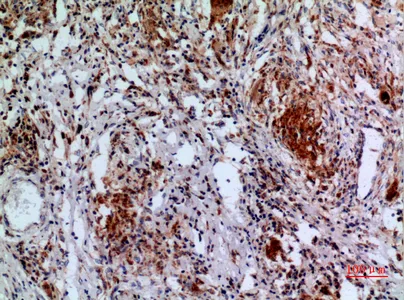

P-Selectin Rabbit Polyclonal Antibody

Cat: APRab16595

Size1:50μl Price1:$118

Size2:100μl Price2:$220

Size3:500μl Price3:$980